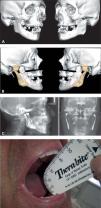

Varón de 55 años, con antecedente de traumatismo facial con fractura sinfisaria conminuta y fractura bicondílea hace 9 años, con secuela de anquilosis articular. Se habían realizado 5 procedimientos quirúrgicos previos, consistentes en resección del bloque anquilótico, artroplastia, injerto autólogo de interposición, osteotomías deslizantes y, por último, reconstrucción de la ATM con prótesis de stock sin resultado satisfactorio. Este paciente presentaba una anquilosis temporomandibular bilateral, con apertura máxima interincisal de 21mm, maloclusión y asimetría facial. La cirugía consistió en: retirada de prótesis de stock y reconstrucción con prótesis aloplásticas bilaterales personalizadas Biomet (fig. 9). Con seguimiento de 24 meses, presenta una MAO de 42mm, estabilidad oclusal y ausencia de clínica en la ATM.

Caso 3 (A-B) Anquilosis articular en paciente con fractura bicondílea de larga evolución. Planificación quirúrgica virtual con prótesis aloplásticas a medida tipo Biomet y osteotomía de LeFort I. (C) Radiología postoperatoria. (D) Máxima apertura oral interincisal de 42mm a los 6 meses de seguimiento.